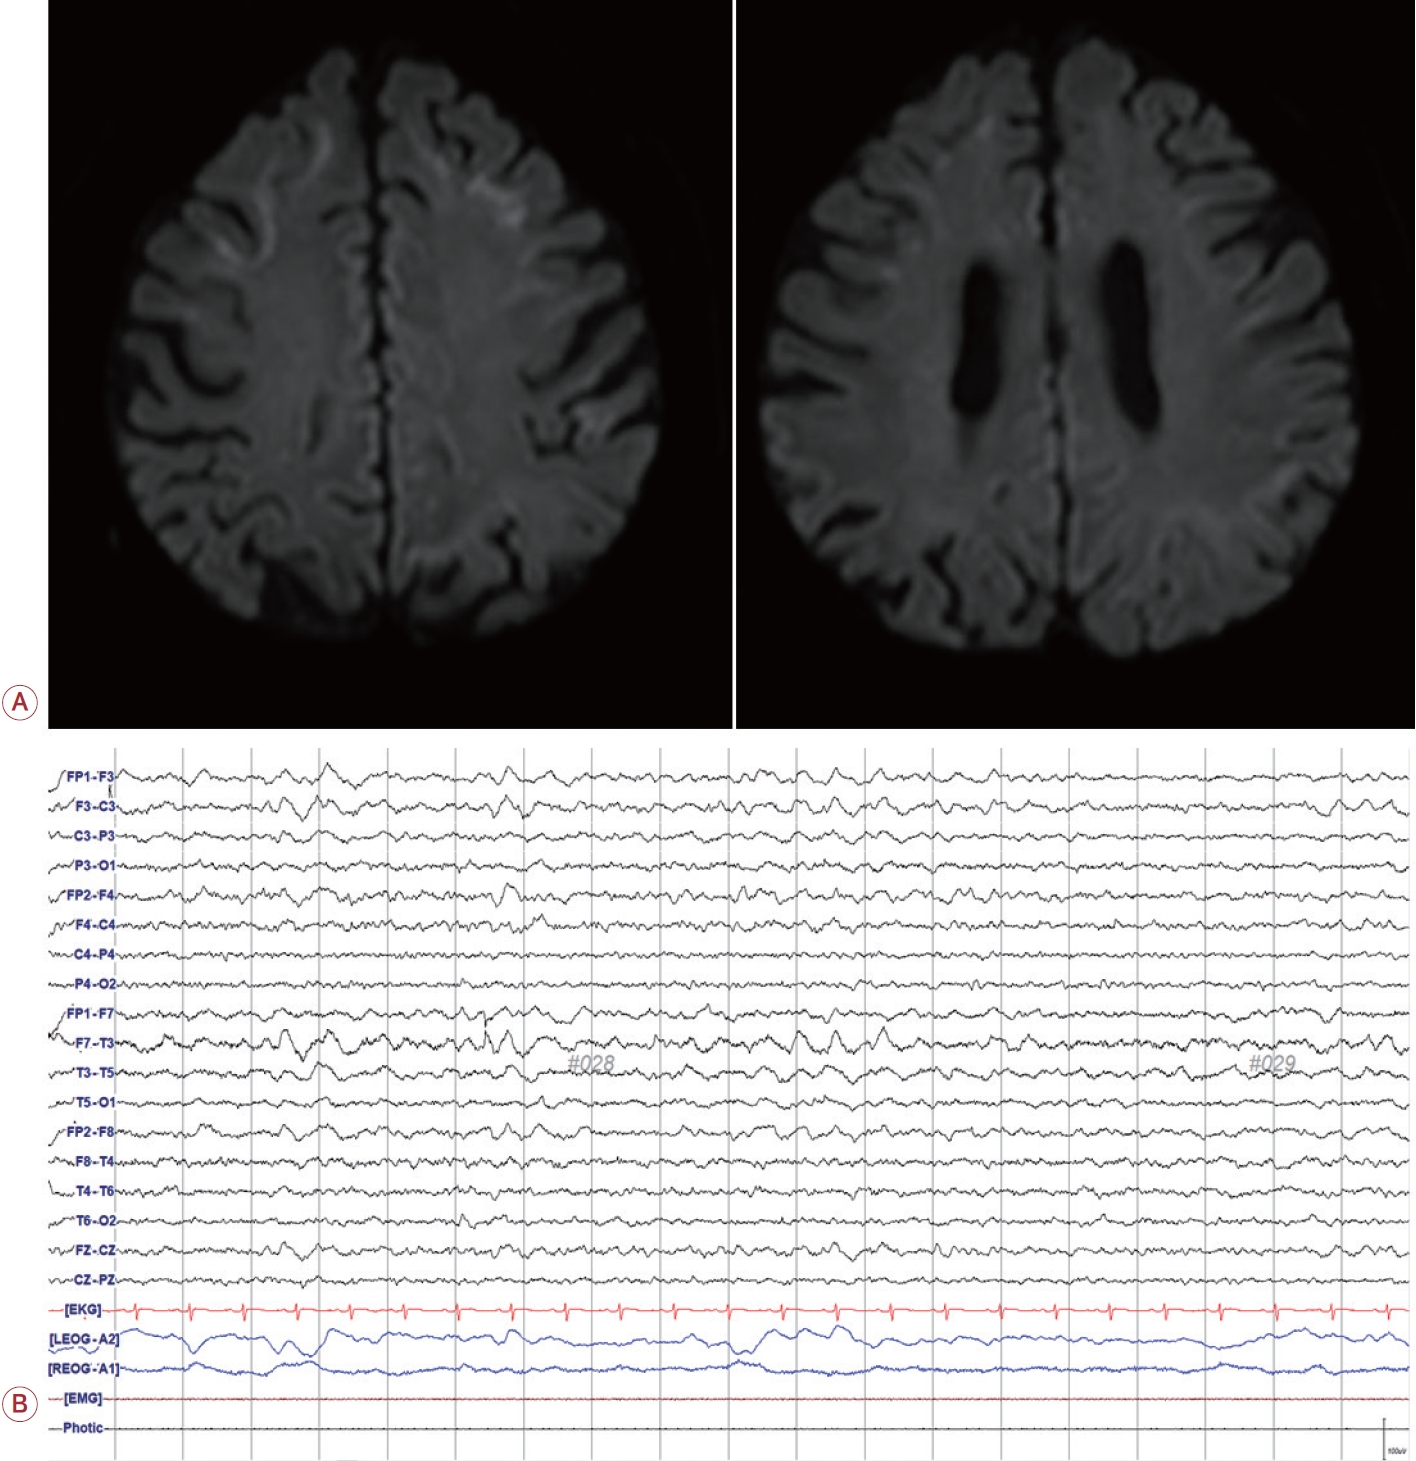

발병 2개월 후 일반 뇌MRI와 DWI를 추적하였으며 좌측 측두엽의 부종 및 고신호강도 소견은 소실되었으나 전두엽 피질 수질접합부의 고신호강도는 지속적으로 확인되었다(Fig. 3). 이에 MRI상 피질수질접합부 고신호강도가 지속되는 소견을 바탕으로 NIID를 의심하였다. 진단을 위해 우측 허벅지에서 피부 생검을 시행하였고 피부 생검 결과 헤마톡실린-에오신(hematoxylin-eosin) 염색에서 땀샘세포의 호산유리질핵내 봉입체가 확인되어 NIID로 진단되었다. 이후 환자는 항경련제를 지속하고 있으며 경련이나 실어증 등 증상의 재발은 없었다.

Figure 3.

Follow-up brain MRI after symptom resolved. Two months after symptom onset, the patient's symptom of aphasia was completely improved. Then we performed a follow-up routine brain MRI with DWI, and a high-intensity lesion with edema in left temporal area was resolved. However, a high intensity lesion of bilateral frontal corticomedullary junction in DWI image was remained. MRI; magnetic resonance imaging, DWI; diffusion weighted image.